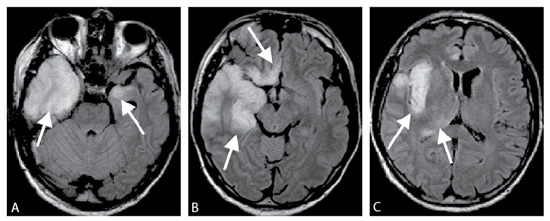

Un patient VIH stade SIDA présente des crises convulsives associées à une ataxie et des troubles visuels. Une IRM est réalisée, quelle est sa séquence, quel est le diagnostic?

IRM, séquence FLAIR.

Leucoencéphalite multifocale progressive car larges plages en hypersignal, confluentes de la substance blanche avec respect du cortex.